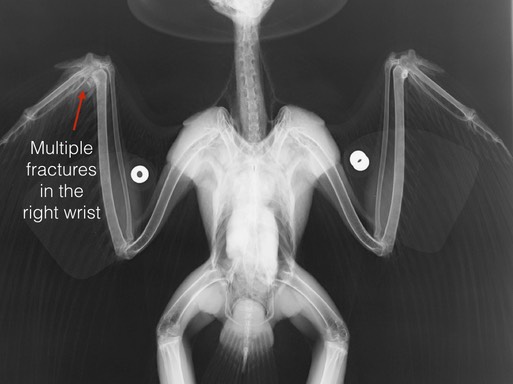

Red-tailed Hawk 19-148

In order to reduce the risk of airplane strikes at the Portland International Airport, Red-tailed Hawks are captured, banded and translocated from the airfield. Hawk N/5 had been observed for some time in the Walla Walla area by volunteer Bill Dunham. Unfortunately, Bill was called on to transport the hawk to BMW’s Pendleton Center after he was hit by a car. The hawk has fractures in his right wrist. The prognosis for a complete recovery is guarded, but we are hopeful.

The interns are keeping busy too. Below Kerry restrains Bald Eagle 19-132 prior to administering his morning treatments. Taylor restrains Red-tailed Hawk 19-148 as he is given oral fluids.